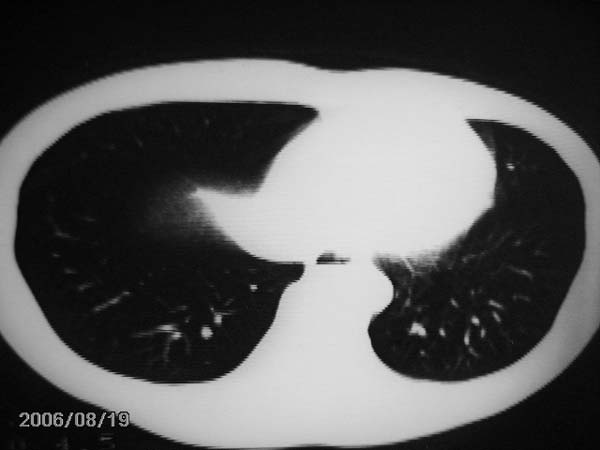

男,13岁,发烧半月,干咳无痰,正规使用抗生素半月,现在仍是午后低烧!!!未做痰检

结合临床考虑:右肺中叶结核可能性大.

右肺中叶结核可能性大

右肺结核,右肺中叶不张

右侧肺门淋巴结好象有增大,会不会是个原发综合症合并感染

右中肺呈大片状密度欠均匀影,内见含气支气管.

结合病史,考虑:右中肺大叶性肺炎(吸收期).

右肺中叶大片状密度增高影,内密度不均匀,右肺门处增大,应该是淋巴结肿大,结合临床首先考虑原发性肺结合可能性大,不排除合并感染可能,建议治疗后复查.